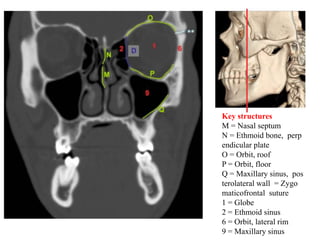

Key structures

M = Nasal septum

N = Ethmoid bone, perp

endicular plate

O = Orbit, roof

P = Orbit, floor

Q = Maxillary sinus, pos

terolateral wall = Zygo

maticofrontal suture

1 = Globe

2 = Ethmoid sinus

6 = Orbit, lateral rim

9 = Maxillary sinus